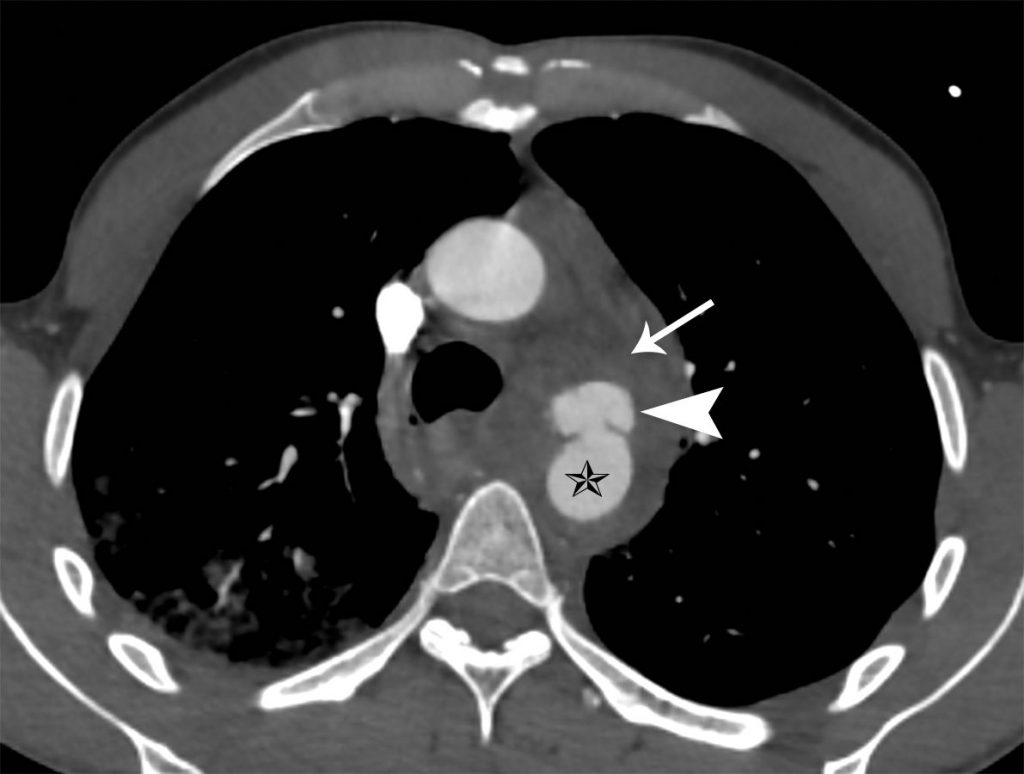

Sur l’angioscanner thoracique, on peut mettre en évidence :

- un flap intimal de dissection localisé à la région isthmique ;

- un hématome de la paroi aortique réduisant la lumière et induisant une hypoperfusion en aval ;

- un faux anévrisme aortique sous la forme d’une dilatation localisée de l’aorte (figure 36.12) ;

- une rupture aortique complète avec un saignement actif.

Fig. 36.12. Angioscanner thoracique montrant la lumière aortique de l’isthme (étoile) déformée à cause de la dissection localisée avec développement d’un faux anévrisme (tête de flèche) et d’un hémomédiastin (flèche).